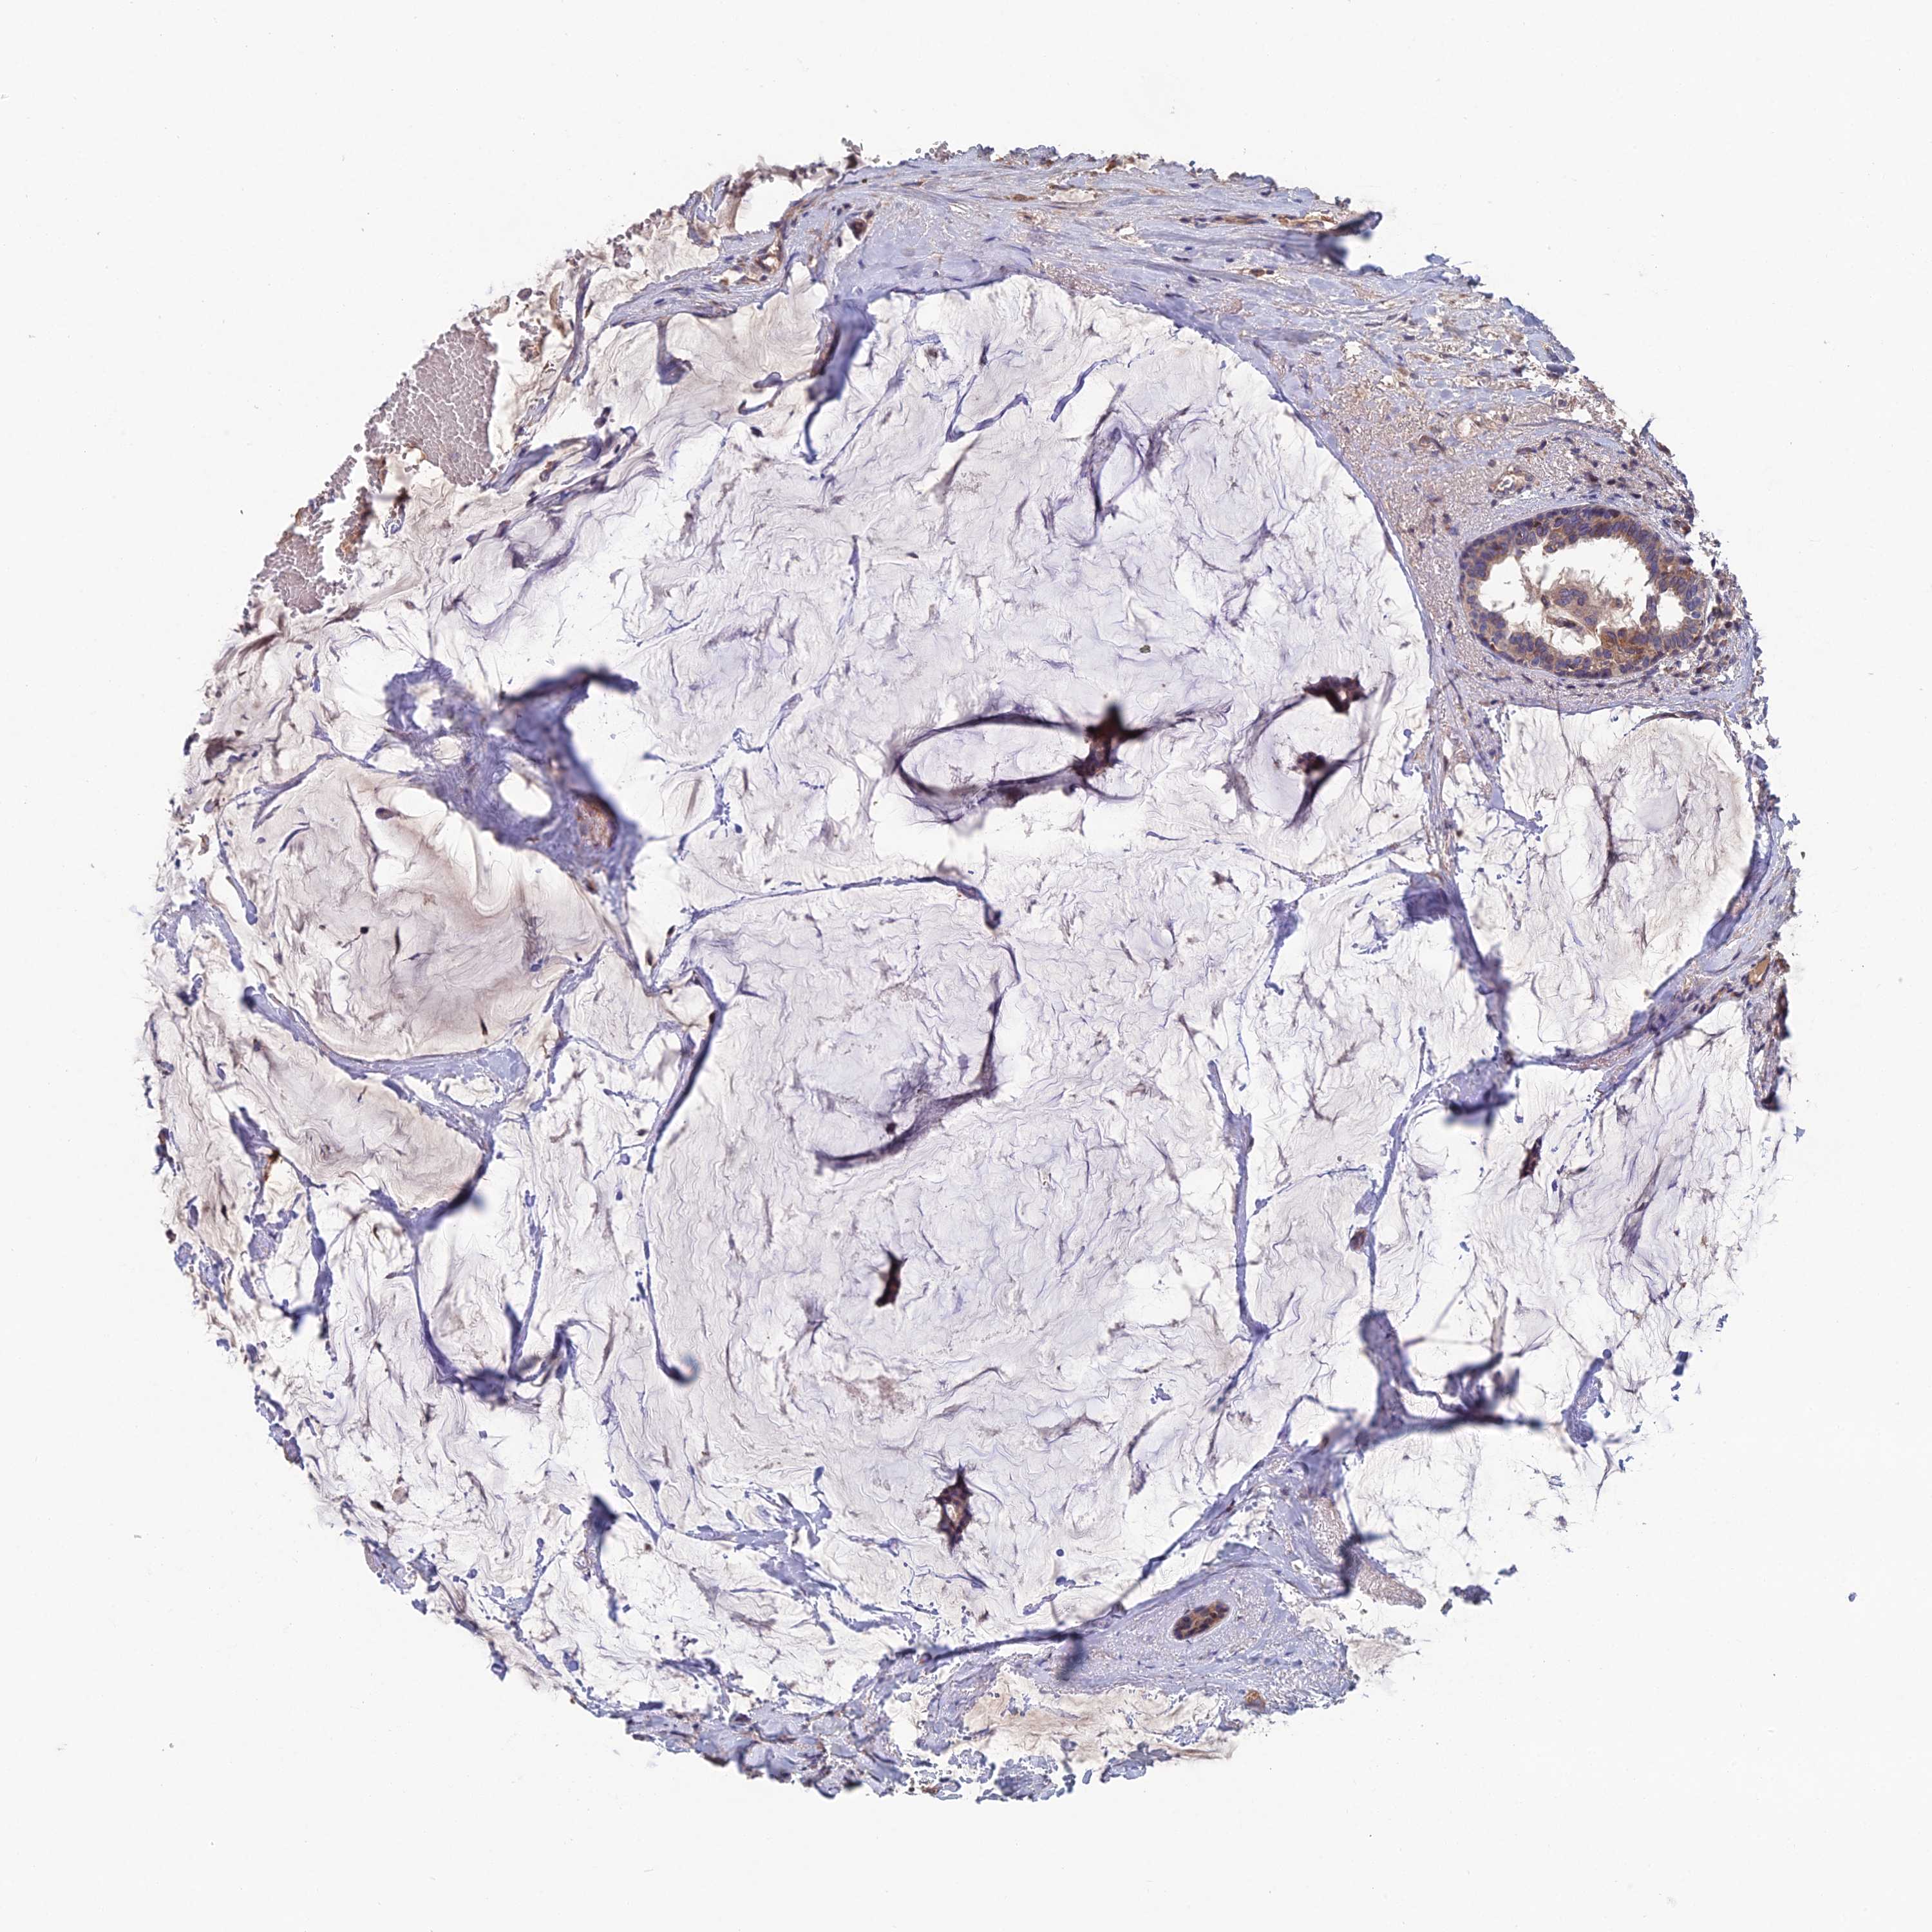

BRCA TCGA BRCA VALIDATION PROTEIN EXPRESSION